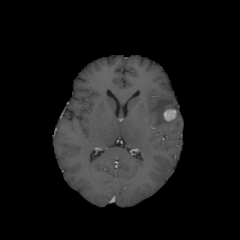

Objectives: This work aims to explore the impact of multicenter data heterogeneity on deep learning brain metastases (BM) autosegmentation performance, and assess the efficacy of an incremental transfer learning technique, namely learning without forgetting (LWF), to improve model generalizability without sharing raw data. Materials and methods: A total of six BM datasets from University Hospital Erlangen (UKER), University Hospital Zurich (USZ), Stanford, UCSF, NYU and BraTS Challenge 2023 on BM segmentation were used for this evaluation. First, the multicenter performance of a convolutional neural network (DeepMedic) for BM autosegmentation was established for exclusive single-center training and for training on pooled data, respectively. Subsequently bilateral collaboration was evaluated, where a UKER pretrained model is shared to another center for further training using transfer learning (TL) either with or without LWF. Results: For single-center training, average F1 scores of BM detection range from 0.625 (NYU) to 0.876 (UKER) on respective single-center test data. Mixed multicenter training notably improves F1 scores at Stanford and NYU, with negligible improvement at other centers. When the UKER pretrained model is applied to USZ, LWF achieves a higher average F1 score (0.839) than naive TL (0.570) and single-center training (0.688) on combined UKER and USZ test data. Naive TL improves sensitivity and contouring accuracy, but compromises precision. Conversely, LWF demonstrates commendable sensitivity, precision and contouring accuracy. When applied to Stanford, similar performance was observed. Conclusion: Data heterogeneity results in varying performance in BM autosegmentation, posing challenges to model generalizability. LWF is a promising approach to peer-to-peer privacy-preserving model training.